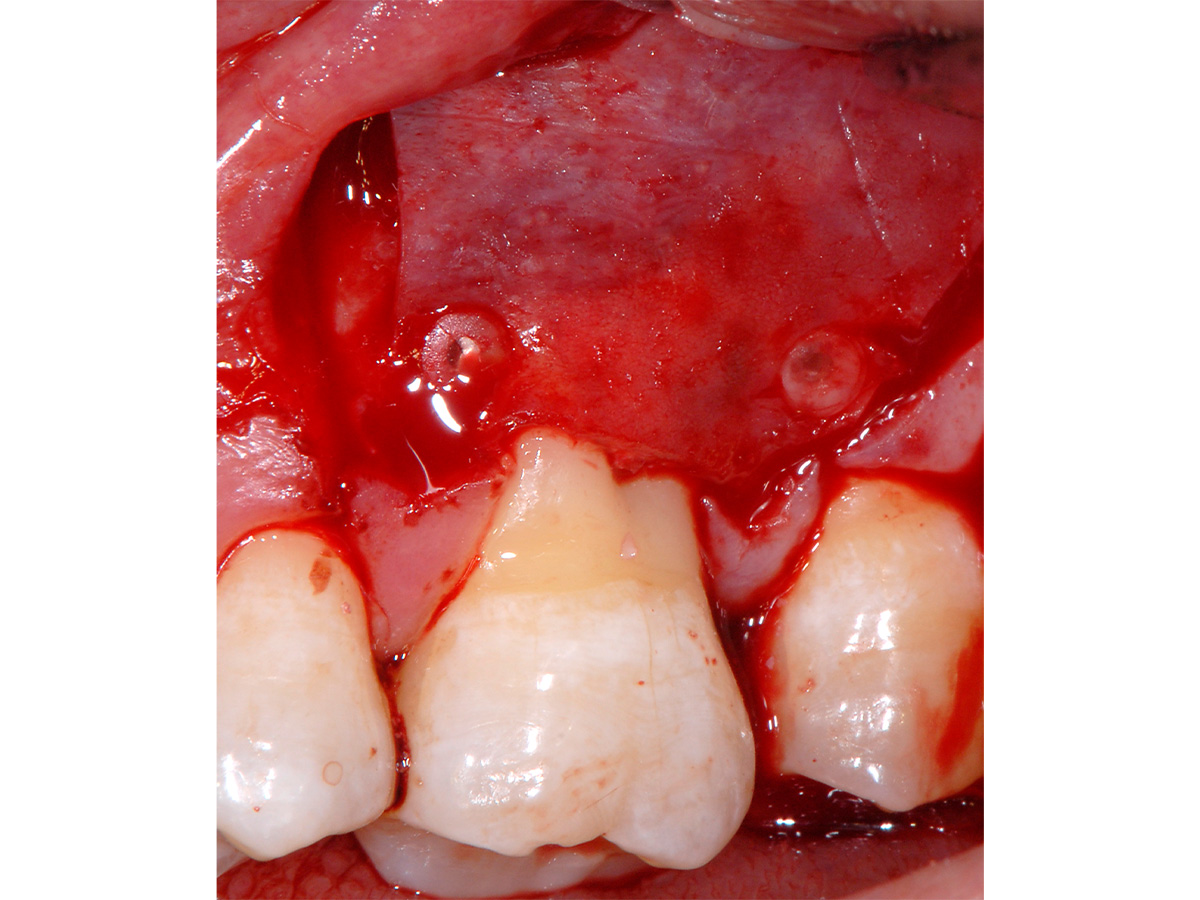

Abbildung 8

Abdecken des Defektes im Sinne von Spacemaking mit einer langsam resorbierbaren xenogenen Barriere (OsteoBiol Soft Cortical Lamina) fixiert mit resorbierbaren Pins (LEADFix).